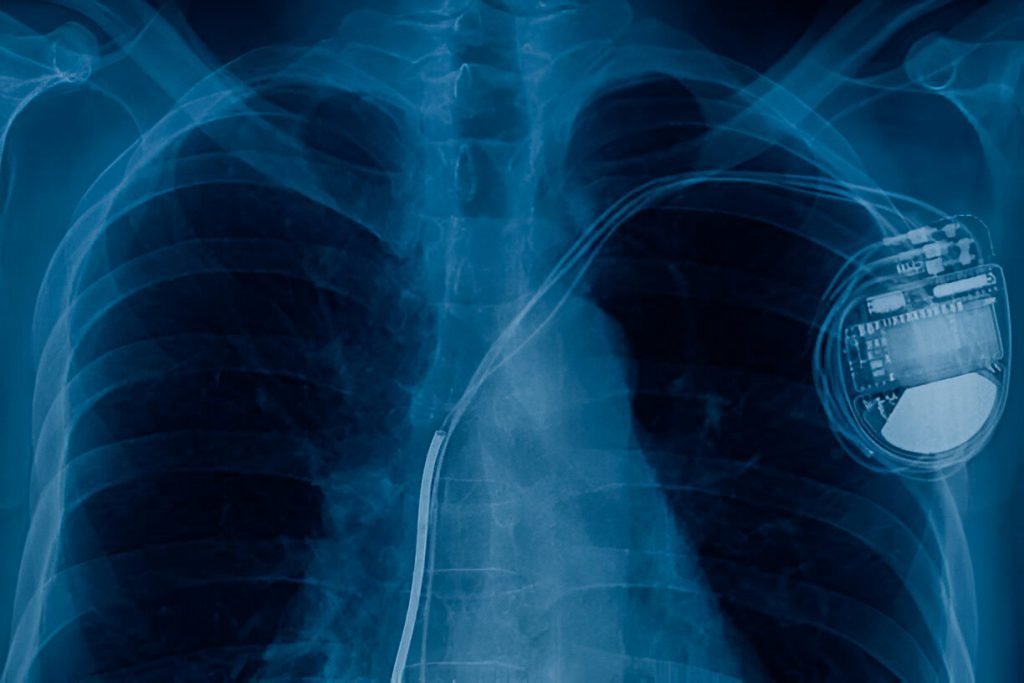

A pacemaker is a small device implanted in the chest to help regulate the heart’s rhythm. It monitors the heart’s electrical activity and, when necessary, sends electrical impulses to stimulate a heartbeat.

A pacemaker consists of a pulse generator (battery and electronic circuitry) and leads (wires) that connect the device to the heart. The pacemaker rhythm is adjusted to meet the specific needs of the patient, ensuring the heart beats at a normal rate.